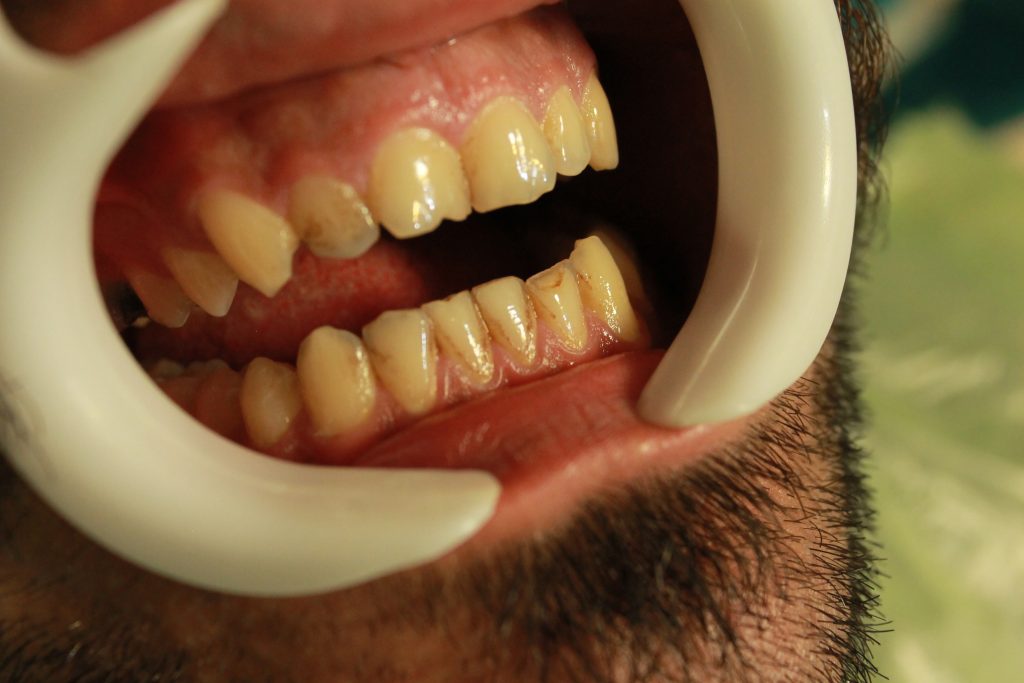

متاسفانه در جامعه ما شایعه خراب شدن مینای دندان در اثر فرایند جرمگیری دندانها، بسیار همه گیر شده است و لذا بسیاری از افراد متاسفانه به دلیل همین تفکر اشتباه به وضعیتهای وحشتناکی دچار میگردند که نمونه ای از آن را مشاهده میکنید.در پاسخ به این افراد باید تاکید نمود که جرمگیری به هیچ وجه در ذات خود اسیبی به دندان و مینای آن نمیزند و برای سلامت دهان و دندان عملی بسیار مهم و لازم محسوب میگردد.همچنین امروزه عمل جرمگیری توسط لوازم التراسونیک انجام میشود که با وارد آوردن نوعی ویبره خاص و قوی ساختار جرم دندان را از هم میپاشد و آنرا از محل استقرارش بر روی دندان کنده و پاک مینماید.همچنین بعد از انجام جرمگیری ،توسط برس و خمیرمخصوصی دندانها پالیش و تمیز می شوند.در کل باید خاطر نشان کرد که جرمگیری میتواند مضر باشد در صورتی که توسط افراد ناوارد و غیر حرفه ای انجام شود.اصولا هر کاری توسط این گونه افراد انجام شود اسیب زا خواهد بود و این امر محدود به جرگیری دندان نمی باشد.بنابراین در انتخاب محل و اشخاص جهت انجام جرمگیری دندان دقت فرمایید.